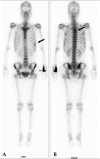

Epithelioid hemangioendothelioma (EHE) is a rare tumor of vascular origin. While it can be found in any tissue, it is most often found in lung and liver and usually has an intermediate behavior. EHEs originating from pleural tissue have been less frequently described than those from other sites. Furthermore, to date, all of the cited pleural EHEs were described as highly aggressive. In the present report, we describe a rare case of pleural EHE extending to lung and bone in a 31-year-old woman. The histological diagnosis was confirmed by both conventional examination and immunohistochemistry. Her disease stabilized during the 4th course of adriamycin (45 mg/m(2), day 1-3), dacarbazine (300 mg/m(2), day 1-3) and ifosfamide (2,500 mg/m(2), day 1-3) with mesna, and she survived for 10 months after the diagnosis.